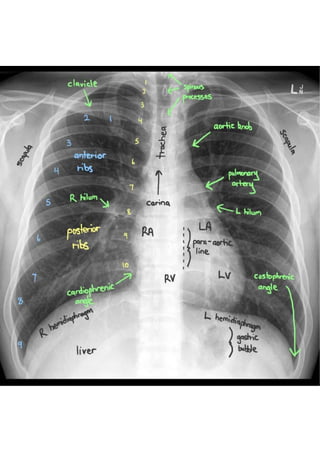

For a childwe don’t talk about chest alone , we talk about chest and abdomen. Baby is small - chest and abdomen fit in one single film. Examine from trachea to periphery . Some prefer to read from periphery to the center. Look at heart and lungs last. Look both domes of diaphragm. Look at costophrenic and cardiophrenic angles.

• 6.

In abdomen lookfor – stomach shadow Transverse colon Rectal gas shadow Near lung fields: All ribs Vertebrae Soft tissue shadows Upper part of femur and humerus also helps in diagnosis.